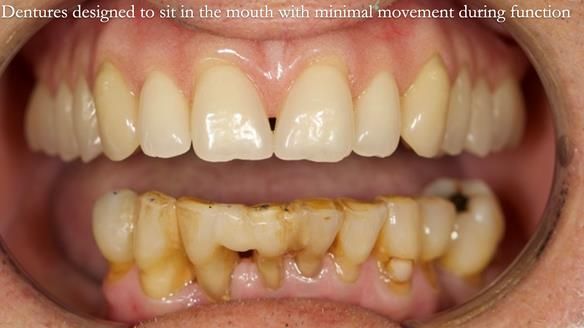

Welcome to my Newsletter 54 showing the making and fitting of dentures (a complete upper metal reinforced denture, a lower immediate partial denture and a definitive Scandinavian designed, metal based lower partial denture) for David, a 75 -year-old man. The full protocol workflow is presented including the use of dentate photographs to mimic his natural teeth.

- Current complete upper denture had many technical problems. Poor retention, support, stability and tissue fit.

- Missing teeth on the lower right side. This makes the upper denture tip when chewing and biting.

- The remaining lower 9 teeth had periodontal disease. Syed Abad, Specialist in Periodontics at the practice managed it.

- The soft tissues of the mouth appeared healthy.